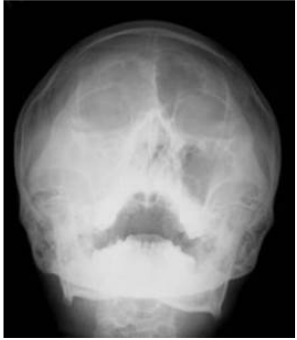

54.患者因右側顎下區(submaxillary region)腫大,尤其在飯後特別腫脹,理學檢查發現右顎 下區摸到一軟性壓痛腫塊,口腔內檢查發現口底唾液腺開口有紅腫,開口處有一黃白色硬 塊。(請依此回答下列3題) 1.下列X光影像何者較能診斷出問題?①skull film(P-A view) ②panoramic film ③occlusal film ④sialogram (A)①②③ (B)②③④ (C)①③④ (D)只有①④

55.2.依下圖口內彩色照片,及X光咬合片影像,下列何種診斷正確?

(A)口底腫瘤 (B)唾液結石堵塞於Stensen’s duct (C)唾液結石堵塞於Wharton’s duct (D)此問題是由舌下腺引起的

56.3.該患者應如何處置?①將口底紅腫塊切除 ②將堵塞之黃白硬塊,以牙科檢查用之forceps 反夾後,在其表面黏膜切開擠出硬塊即可 ③給予抗生素 ④鼓勵術後多喝水 (A)①③④ (B)只有②③ (C)只有③④ (D)②③④